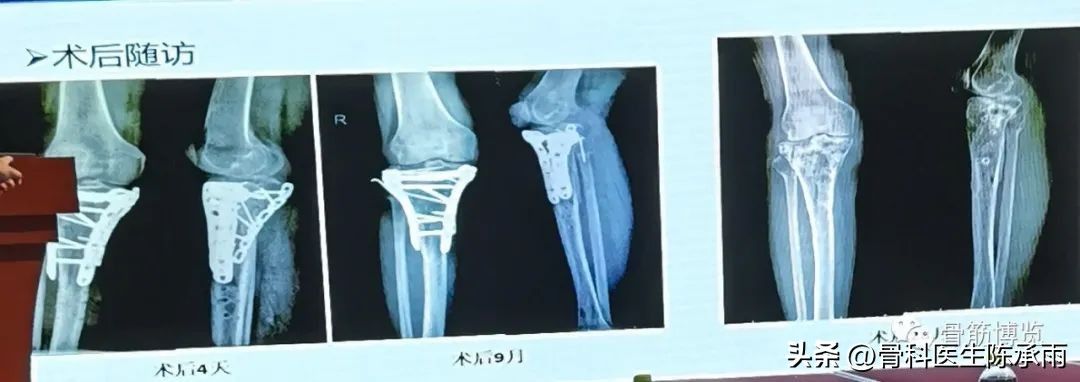

胫骨平台骨折的分型比较多,我们临床上常用的就是Schatzker分型和AO骨折的分型,还有骨折脱位的Hohi-Moore分型,这是我们常用的三个分型。

对AO 分型来讲,现在这是AO推出来更详细的,再分为ABC。随着分型的增加,从A到C骨折的损伤程度是越来越重,治疗也越来越困难,从1到2 ,123也是这个规律,骨折的分型就是给我们表明了骨折的一个损伤的程度,治疗办法和损伤的特点。我们对于骨折脱位的分型,常用Hohi-Moore分型,这个是弥补了,Schatzker和AO分型的一些缺陷。